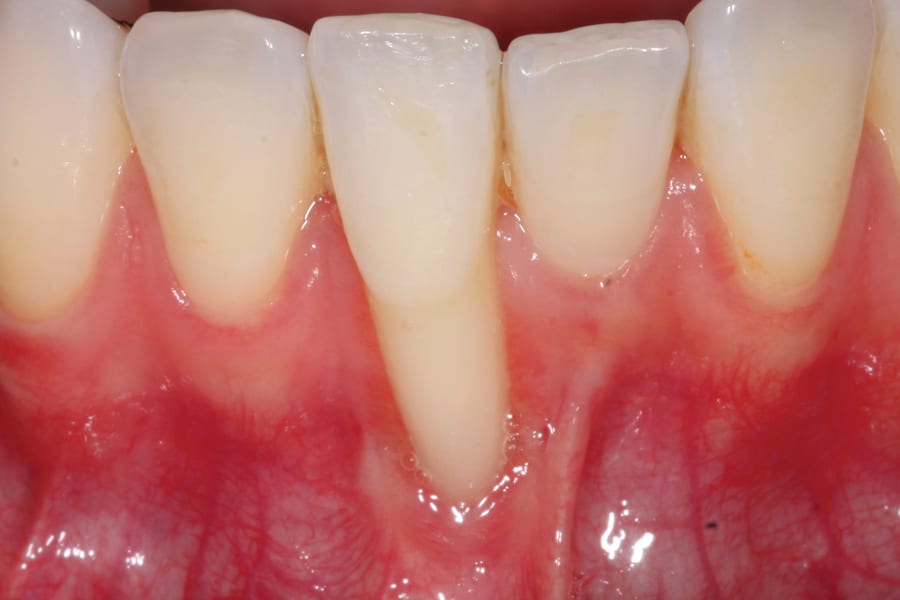

There are, however, some unfavorable long-term ramifications of this design. Due to the nature of stainless steel, which has memory and over time will partially return to its original shape, these twisted lingual retainers may "unwind" or uncoil and exert unintended forces on the teeth to which they are bonded (Figure 5 and Figure 6, Figure 8 through Figure 11, Figure 14 through Figure 16). This leads to excessive labial or lingual root torquing movements, often resulting in highly undesirable recessions, dehiscences, and fenestrations. Because it may take years for this occurrence to manifest, the orthodontist (who usually places the retainer) is typically both unaware of the situation, as he or she does not customarily follow patients for such long-term periods, and free of blame. The periodontal implications of this outcome can be highly detrimental, as seen in the cases presented herein.

Once deformities, such as an undesirable dehiscence or root position, are detected, remedial action should first involve correcting the tooth position. Although this endeavor can take time and be somewhat challenging, it can be accomplished in several ways. First, in all cases, the twisted lingual splint must be removed. Following this, one of three modalities may be used. One is to allow the teeth to relapse. This may not be the most desirable option, as it may also incur other untoward movements, such as allowing the teeth to return to the pretreatment positions. Further, this option will likely be slow to progress.

A second option is to use corrective orthodontic therapy in the form of fixed appliance application to torque the root back into the correct position (Figure 5 through Figure 7). This requires full-sized archwire insertion into a precision edgewise bracket (Figure 7). This can be a time-consuming undertaking, as the step-up through various archwires until fully engaging a full-sized wire will take a few months. Nevertheless, significant corrective changes often can be observed, as the tooth's investing structures often spontaneously remodel, at least partially, in response to the corrected tooth position (Figure 5 and Figure 7, Figure 11 and Figure 13).